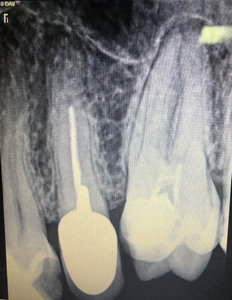

Попала к девушке со стажем работы 1 месяц. Мне удаляли нервы, но не смогли полноценно запломбировать зуб. Только один из каналов вроде запломбировали, т.к. из канала шла кровь, и они не могли её остановить. Прижигали мне там что-то по 10 раз. Поставили временную пломбу, а под нее вату. На следующий день тоже самое, на помощь молодому врачу подключилась врач со стажем. Она посверлила еще и нашла еще один канал. Опять прижигали. Шептались постоянно, я услышала фразу про две перфорации. Послали на рентген. Следующий прием только через 3 дня. К ней точно не пойду, уже нет доверия. Это была стоматология по ОМС. Пойду в платную стоматологию, может, спасут зуб.

По снимку, определить о какой перфорации шептались Ваши врачи, не представляется возможным.